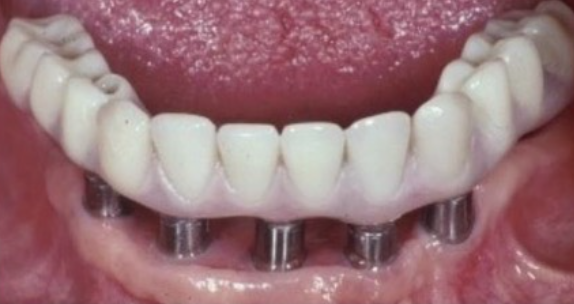

Many factors should be considered when designing implant-supported restorations to reduce the risk of peri-implantitis affecting physical removal of bacterial plaque at the FMG. Included are oral hygiene devices, accessibility, prosthetic shapes, and patient ability to comply with oral hygiene procedures. The design should be conveniently hygienic so patients can easily comply with the recommended oral hygiene procedures. Physical removal of bacterial plaque on the intaglio surface at and above the FMG reduces the risk of peri-implantitis in the sub-gingival transmucosal tissue around dental implants. The original fixed prosthetic design presented by Branemark, a "High water design", provided access to all surfaces for oral hygiene management without a patient complaint of food accumulation (Figure 9 and Figure 10). Notably, relief above the gingiva was not patient complaint with this design. Lack of embrasure access to the FMG and intaglio surfaces for oral hygiene management can lead to peri-implantitis (Figure 11 and Figure 12). Stein recommended a convex modified ridgelap pontic design with lingual and palatal access to facilitate plaque removal from the intaglio surface under pontics in fixed prosthetics with dental floss.20 These shapes should be standard for fixed implant-supported restorations whether individual or multi-unit restorations made of ceramo-metal or milled zirconia (Figure 13 through Figure 16).

(9.) Branemark “High water” design.

Figure 9

(10.) Branemark “High water” design.

Figure 10